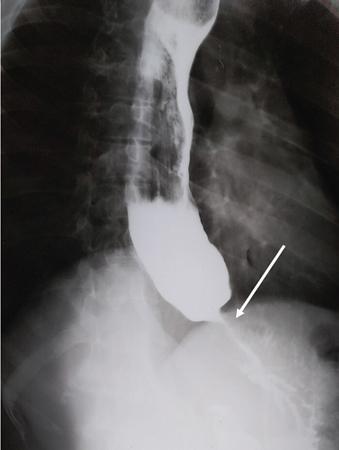

Single contrast barium study (Fig. 7.4.5.1), CECT (Figs. 7.4.5.2 and 7.4.5.3).

Fig 7.4.5.1 Barium study of the patient.

Observations

Barium study shows large filling defect in the antrum forming acute angles with the wall. Undulating contour is seen along greater curvature with ulceration of overlying mucosal irregularity.

CECT shows a large lobulated mass involving lesser curvature and antrum with marked wall thickening along distal greater curvature.

Diagnosis

Carcinoma stomach.